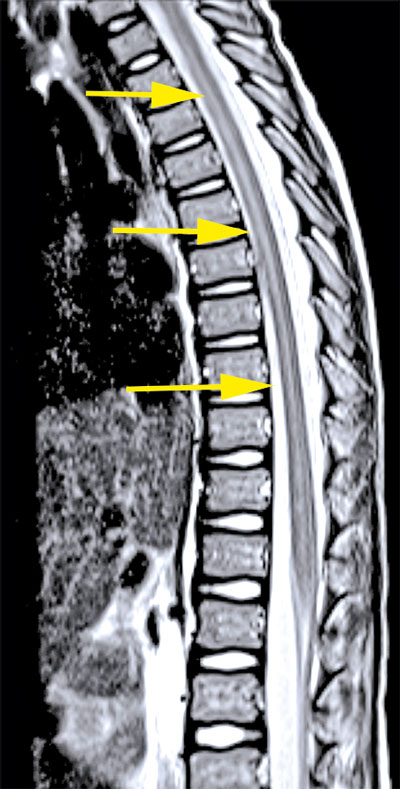

Omfattande mikrobiologisk utredning genomfördes, inklusive prov från likvor, blod, feces m m. Nasofarynxaspirat kontrollerades 10 dagar efter det att han först insjuknat och utföll positivt för enterovirus. Senare typning påvisade EV-D68. MR visade fokala signalförändringar i pons och medulla oblongata samt långsträckta signalförändringar över flera nivåer i ryggmärgens gråa substans utan kontrastmedelsupptag som vid en långsträckt central myelit (Figur 2).

Upprepad MR-undersökning efter drygt 2 veckor visade att signalförändringarna i ryggmärgen hade gått i regress men att det tillkommit kontrastupptag i cervikala och lumbala nervrötter (Figur 2). Neurofysiologiska undersökningar med EnEG, EMG och motoriska reaktionspotentialer 1 månad efter insjuknandet visade tecken på uttalad påverkan av nedre motorneuron i undersökta myotom på vänster sida och en generellt förlängd central överledningstid till undersökta segment på samma sida, vilket talade för påverkan även på centrala motoriska banor.

Figur 2 (fall 2). Vid initial MR-undersökning visade T2-viktad sekvens långsträckta signalförändringar i hela ryggmärgen (första bilden) samt fokalt i bakre delen av pons (andra bilden). Axialt i höjd med C2 påvisades engagerad grå substans (tredje bilden). Vid uppföljande MR-undersökning visade T1-viktad sekvens över halsryggmärgen (sista bilden) endast kontrastladdning i nervrötter.